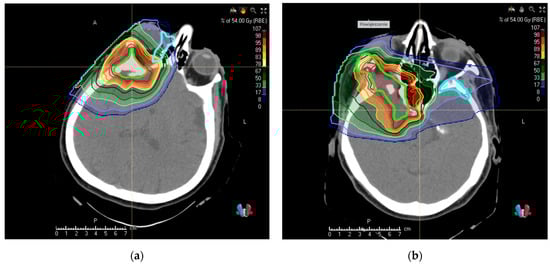

For depicting dosimetric consequences of target volume change after recontouring with PET/CT, we selected patients with the newly found critical tumor extension. New PBT treatment plans according to the protocol described in the Methods Section were created for target volumes performed by using MRI only; PET/CT-assisted volumes were subsequently appended to display the possible underdosage. These are displayed in Figure 2a,b; the relevant dosimetric statistics are displayed in Table 2.

Figure 2.

Display of dosimetric consequences of omission of tumor volume in two cases in which PET/CT delivered new crucial information in addition to CT + MRI. Thick fluorescent contours represent volumes of observers performed using MRI only, thick light blue contours display the newly identified tumor extent: (a) intraorbital (b) in the left sphenoid bone. The treatment plans were carried out for MRI volumes only.

Table 2.

Dosimetric evaluation of cases with critical new information delivered by [68Ga]Ga-DOTA PET/CT.